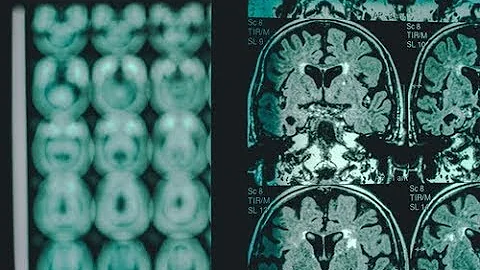

Alzheimer's Disease: Pursuing The Cure

World renowned Alzheimer's disease researcher Huntington Potter, M.D., talks about a drug that has shown promise in inhibiting ...